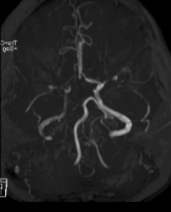

神经介入诊疗中心主任、副主任医师刘俊中接诊后,根据各项检查检验结果迅速判断张女士属于颅内大血管病变。

左侧大脑中动脉和颈内动脉均已闭塞,相当于左侧大脑半球几乎断了供血,手术指征明确。

5 分钟后,张女士被推进介入手术室,急诊脑血管造影进一步确认了血管闭塞情况。